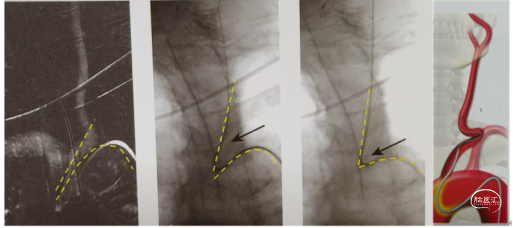

5)男性患者或桡动脉相对粗大的患者在没有7F薄壁桡动脉鞘的情况下,先置入5F桡动脉鞘,将0.035in泥鳅导丝置于肘关节以上,保留导丝撤出桡动脉鞘,沿泥鳅导丝将带有内芯的6F Nueron MAX 长鞘输送至前臂近肘部,撤出内芯,泥鳅导丝携带130-140cm 长sim导管和Nueron MAX 长鞘同轴到达锁骨下动脉段,泥鳅导丝携带长sim导管在主动脉降部起始部成袢或泥鳅导丝小心通过主动脉开口到达颈总动脉,保持泥鳅导丝固定,输送长sim 导管弯头段通过主动脉开口部位U型泥鳅导丝弯,撤出泥鳅导丝成袢。

成袢后回拉sim导管超选颈总动脉,旋转sim导管解袢呈“勾型”,将泥鳅导丝走行颈内动脉起到支撑作用,同轴输送Nueron MAX 长鞘到达颈内动脉远端建立稳定的血管通路,撤出长sim导管,泥鳅导丝或微导丝、微导管导引下沿Nueron MAX 长鞘将中间导管顺利输送至病变目标血管进行抽吸取栓或支架取栓。下图1-4所示。